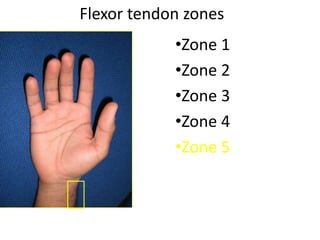

- It describes flexor tendon zones, extensor compartments, and pulley system anatomy.